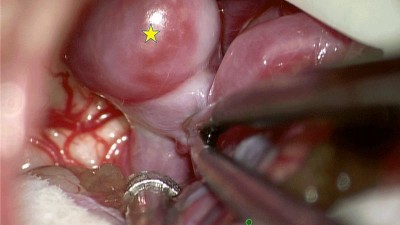

Marek stále neměl vyhráno, po amputaci jej čekala další operace ruky a druhé nohy. „Domů jej pustili 17. září, tedy měsíc po nehodě. Teď se učí být samostatný, rehabilituje. To vše stojí mnoho peněz, byli bychom šťastní, kdyby mohl získat kvalitní protézu, aby se mohl zase postavit na obě nohy," uzavírá Martina Vítková.